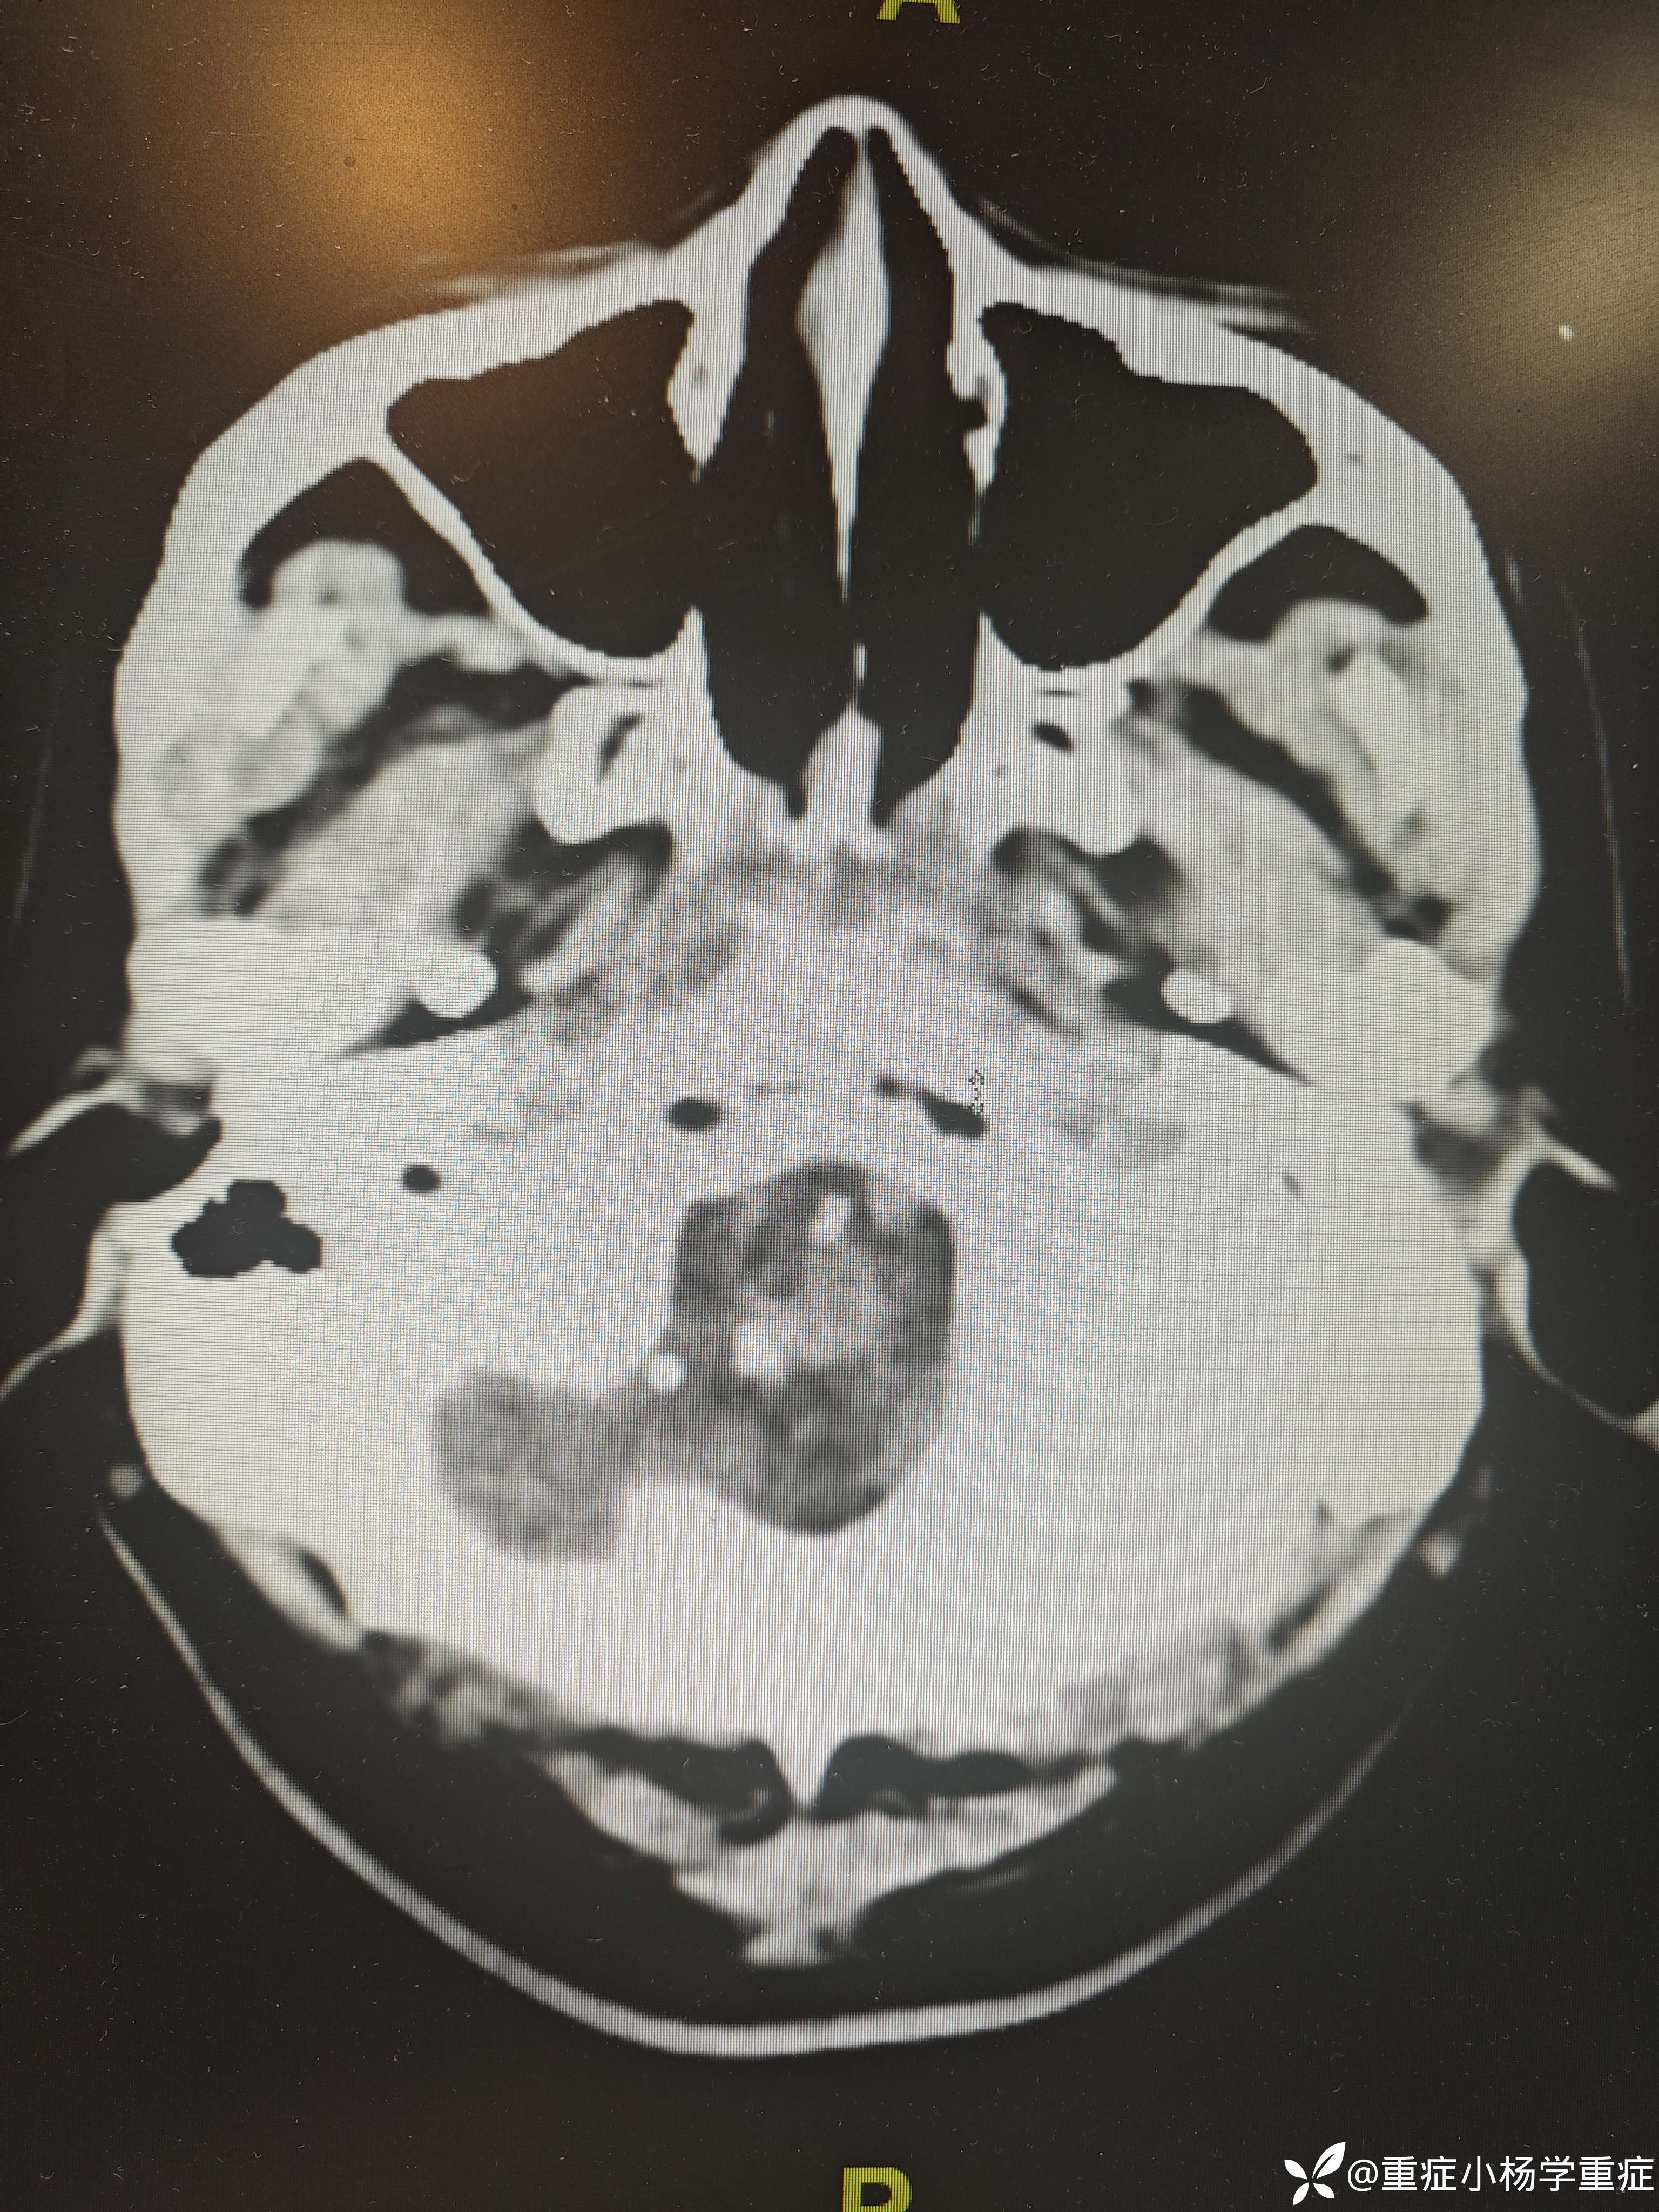

飞跃迷雾1 达人已点赞因“代:脑出血术后2月余,痰多伴呼吸困难1小时”入院。因头痛至医院检查ct提示蛛网膜下腔出血,后完善CTA提示脑血管畸形,至省内医院行介入栓塞后出现脑梗塞,考虑压迫延髓导致呼吸功能损伤,术后第二天予以气切,后出现四肢瘫痪,近期ct如下